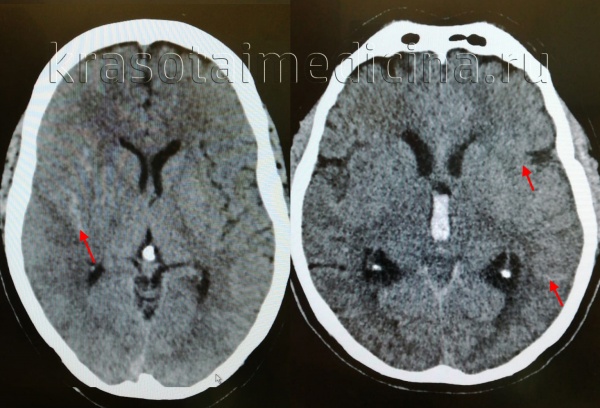

(а) Рисунок больших полушарий головного мозга, вид сверху: синим цветом изображено конвекситальное субарахноидальное кровоизлияние (САК), распространяющееся на соседние борозды, но не затрагивающие базальные цистерны.

(б) Бесконтрастная КТ, аксиальный срез: у женщины 28 лет с интенсивной головной болью, возникшей после родов, определяется ограниченное субарахноидальное кровоизлияние, локализующееся над конвекситальной поверхностью правого полушария. (а) MPT, Т1 -ВИ, аксиальный срез: у этой же пациентки в бороздах конвекситальной поверхности правого полушария определяется «грязный» ликвор (по сравнению с нормальной гипоинтенсивной СМЖ в контрлатеральных бороздах).

(б) MPT, FLAIR, аксиальный срез: у того же пациента в области борозд конвекситальной поверхности правого полушария определяется гиперинтенсивный сигнал (в противоположность гипоинтенсивному подавленному сигна лу от нормальной СМЖ в области борозд конвекситальной поверхности левого полушария).

Постнатально по результатам ЦСА была диагностирована васкулопатия (снимки не представлены).